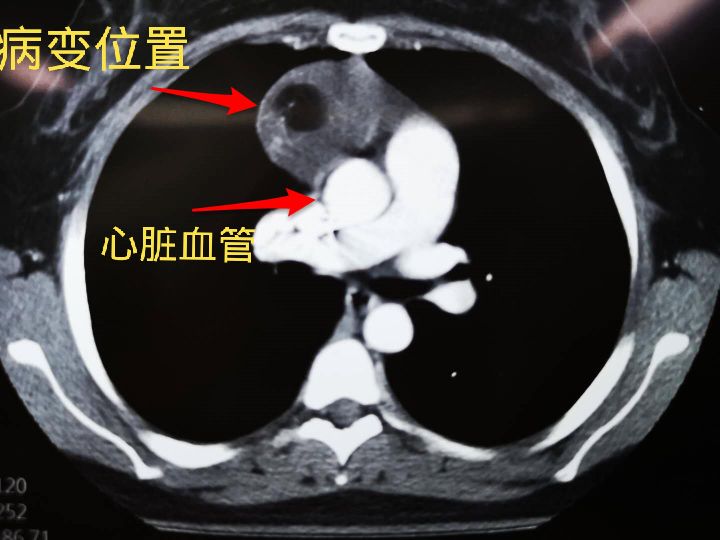

虽然小燕的畸胎瘤是良性,但不好的消息是这个畸胎瘤长的位置很危险,恰好长在了心脏血管旁边!下图中白色的部分就是心血管的横截面,灰色阴影部分就是畸胎瘤。可以看出,这颗畸胎瘤挨着心脏血管挨得很紧,必须切除,如果因为畸胎瘤造成心血管破裂出血,后果不堪设想。

小燕的肿瘤,长在主动脉和上腔静脉的间隙,周围都是大血管。就像一颗巨蛋躺在血管围成的巢里。